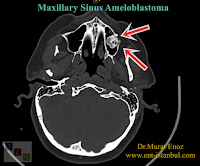

A 56-year-old female patient was diagnosed with chronic sinusitis in a different clinic where she presented with pain on the left maxillary sinus, and the patient was scheduled for anterior plan medical treatment and then functional endoscopic sinus surgery at there. The patient admitted us to schedule an operation for a simple endoscopic sinus surgery operation. Paranasal sinus tomography of the patient (before receiving medical treatment, in the presence of severe sinusitis) shows an opaque, irregular lesion originating from the left maxillary sinus floor. Thin-section paranasal sinus tomography, which was requested after the nasal and oral cortisone treatment given to the patient, revealed a massive tumoral lesion with a size of 14-12 mm, originating from the left maxillary sinus floor and compatible with "Ameloblastoma".

Symptoms of paranasal sinus tumors can sometimes be almost the same as a simple sinusitis. Unfortunately, the diagnosis can be delayed with certain vague symptoms such as facial pain and infection in the affected sinuses. As in this patient, when the inside of the left maxillary sinus is filled with inflammatory secretion, it may be difficult to notice the tumoral mass or it may not be noticed if the tumor is too small. In case of accidental follow-up and medical treatment, it may cause the tumor to spread locally invasively. In the video above, a tumoral mass in the maxillary sinus is seen more clearly and distinctly after medical treatment.

Below you can find other tomography images of the patient. I took a photo directly on the laptop, a little blurry.